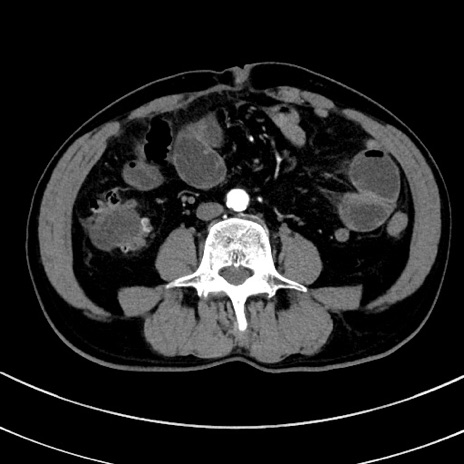

冠状断像

【症例】 60歳代男性

【主訴】 黒色吐物

【現病歴】 4日前から嘔気自覚、2日前の朝食後にも嘔気あり、自分で手で嘔吐反射起こし嘔吐したところ血が混ざっていたため受診。

【既往歴】 5年前汎発性腹膜炎を伴う急性虫垂炎で手術、高血圧、前立腺肥大症、高脂血症

【身体所見】 腹部正中に手術癩痕あり 腹部平坦・軟圧痛なし膨満感あり

【データ】WBC 8400、CRP 4.54